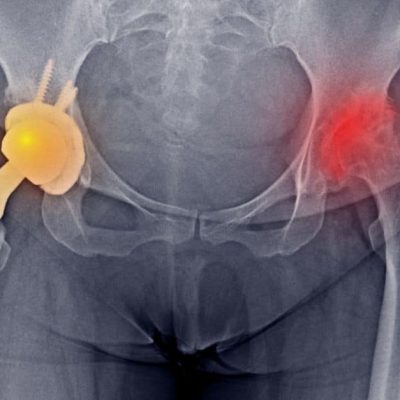

درد لگن سمت چپ و پای چپ

سلام، من دکتر محمد‌رضا کاظمی، فلوشیپ فوق‌تخصصی درد هستم و امروز می‌خواهم با شما در مورد علت درد لگن سمت چپ و پای چپ صحبت کنم. شاید شما ...